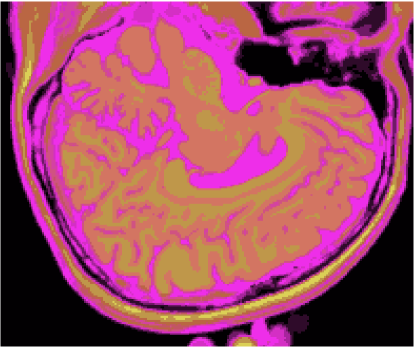

As figuras 2 (banda 0), 3 (banda 1) e 4 (banda 2) mostram a fatia 97 de um volume de imagens sagitais com 181 fatias e 0% de ruído, ponderadas em PD (densidade de próton), T1subscript𝑇1T_{1} e T2subscript𝑇2T_{2}, enquanto a figura 5 ilustra a composição colorida R0-G1-B2 da mesma fatia. Pode-se notar no topo do crânio, na parte inferior das imagens, a presença de artefatos, que podem ser resultantes de erros no simulador, mas que não são prejudiciais à análise, uma vez que, neste trabalho, não é dada ênfase à análise anatômica.

Figura 2: Imagem de RM da fatia 97 ponderada em PD

Figura 3: Imagem de RM da fatia 97 ponderada em T1subscript𝑇1T_{1}

Figura 4: Imagem de RM da fatia 97 ponderada em T2subscript𝑇2T_{2}

Figura 5: Composição colorida R0-G1-B2 das imagens da fatia 97 ponderadas em PD, T1subscript𝑇1T_{1} e T2subscript𝑇2T_{2}

3.1 Classificadores Dialéticos Objetivos

A figura 6 mostra os resultados de classificação, enquanto a figura 7 exibe os resultados de quantização para a imagem sem ruído da fatia 97, figura 5, usando os métodos KO, CM, KM, ODC-PME e ODC-CAN. Esses resultados ilustram qualitativamente as diferenças entre os métodos de classificação e quantização, dado que a fatia 97 possui todas as 13 classes presentes na análise [51].

Figura 6: Composição colorida R0-G1-B2 das imagens da fatia 97 ponderadas em PD, T1subscript𝑇1T_{1} e T2subscript𝑇2T_{2} (a) e resultados de classificação usando os métodos KO (b), CM (c), KM (d), ODC-PME (e) e ODC-CAN (f)